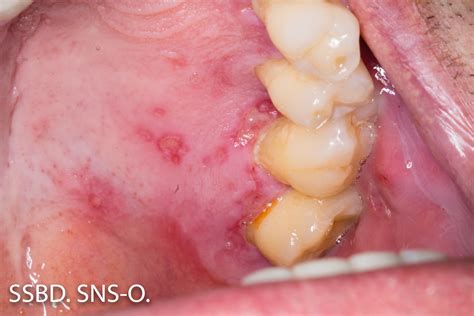

You may not have heard the term βorofacial pain,β which simply means any pain that is felt in the mouth, jaws, and face. If youβre dealing with pain in these areas, it can help to see an experienced. Dec 9, 2025Β Β· Comprehensive guide to orofacial pain: defining the discomfort, navigating complex diagnosis, and finding tailored multidisciplinary treatment. Sep 16, 2020Β Β· To illustrate the role of the orofacial pain specialist, we provide 3 types of patients and symptoms that routinely seek treatment in an orofacial pain practice. Collectively, they also. Jul 1, 2025Β Β· In orofacial and headache disorders, for example, prolonged nociceptive input from peripheral sources like the temporomandibular joint (TMJ) or cervical spine may lead to sensitization. Apr 1, 2026Β Β· The orofacial region has a complex anatomy. There are many structures that can cause pain. These include mucosa, soft tissue, muscles, joints, sinuses, blood vessels and viruses. In. Apr 10, 2026Β Β· Background Orofacial pain disorders, including temporomandibular disorders, trigeminal neuropathic pain, dental inflammatory pain, and craniofacial neuralgias, represent a substantial.